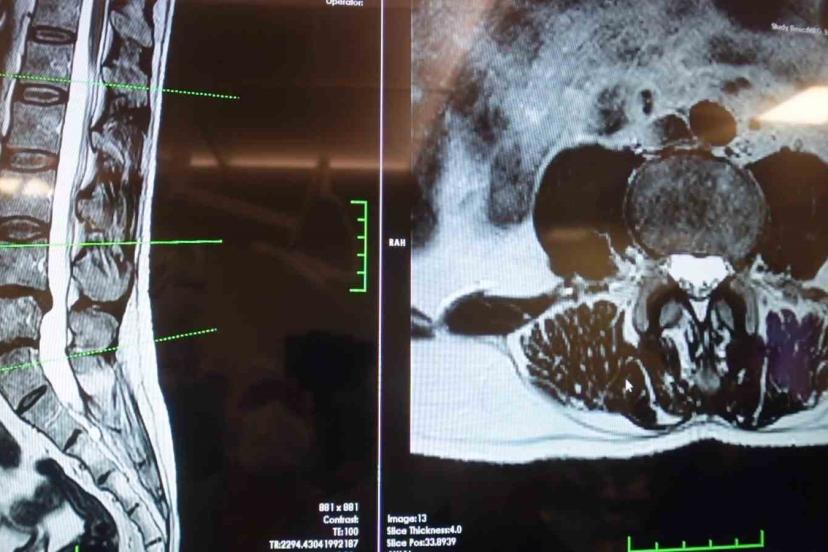

Elazığ Fırat Üniversitesi Hastanesi Beyin ve Sinir Cerrahisi Anabilim Dalı Başkanı Prof. Dr. Fatih Serhat Erol, bel fıtığı hastalığı hakkında açıklamalarda bulundu. Beyin ve sinir cerrahisi pratiğinde sık karşılaşılan hasta gruplarından birinin omurga hastaları olduğunu belirten Prof. Dr. Erol, "Boyun ve sırt omurlarının yanı sıra en çok bel bölgesiyle ilgili sorunlar görülüyor. Bel fıtığı önemli bir hastalıktır. Bel ağrılarının büyük bir kısmının bel fıtığından değil, mekanik bel ağrısından kaynaklanıyor. Mekanik bel ağrısının kaslar, eklemler, iskelet sistemi ve bu yapıları birbirine bağlayan bağların uzun süreli zorlanması sonucu ortaya çıkmaktadır. Bu durumun hastalarda şiddetli bel ağrısına neden olabilir. Mekanik bel ağrısının bel fıtığı ile karıştırılmaması gerekiyor. Bel fıtığına kıyasla mekanik bel ağrıları çok daha sık görülüyor. Bir diğer önemli hasta grubu ise omurilik kanal darlığı olan hastalardır. Bu hastalıkta dejeneratif süreçler sonucunda omurilik kanalında ve sinir köklerinin geçtiği kemik kanallarda daralma ve kireçlenme meydana geliyor. Bu durumun omurilik ve sinir köklerinde sıkışmaya yol açar. Hastaların ayakta dururken ya da yürürken bel, kalça ve bacaklara yayılan şiddetli ağrılar hissettiğini, yürüyüş mesafesi arttıkça oturup dinlenme ihtiyacı duyarlar. Tedavi sürecinin doğru tanıya göre belirleniyor. Bel ve bacak ağrısı şikayeti olan hastaların mutlaka bir beyin ve sinir cerrahisi uzmanına başvurması gerekiyor. Hastaların şikayetlerinin dinlenmesi, gerekli muayene ve tetkiklerin yapılmasının ardından hastalıkların birbirinden ayırt edilebildiğini ve buna uygun tedavi planının oluşturulur" cümlelerini kullandı.